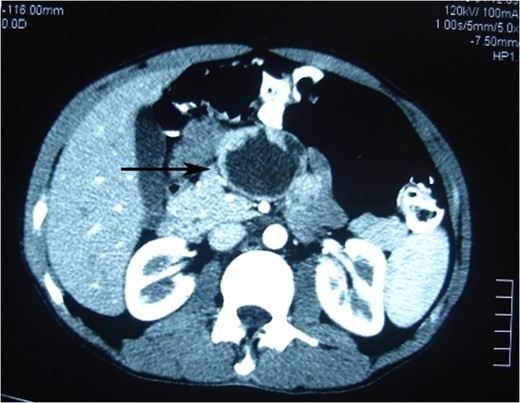

Photomicrograph of the arterial phase CT showing well-circumscribed low attenuated lesion (arrow).

Ultrasonographically, the tumor is well encapsulated, homogeneous or heterogeneous, and composed of solid echogenic and hypoechogenic cystic components [10]. CT scan usually demonstrates a well-encapsulated and circumscribed retroperitoneal mass, hypodense, with various solid and cystic components owing to hemorrhagic degeneration [11]. Magnetic resonance imaging is better than CT for distinguishing certain tissue characteristics, such as hemorrhage, cystic degeneration or the presence of a capsule. Fine needle aspiration cytology has been reserved for selected cases [10].